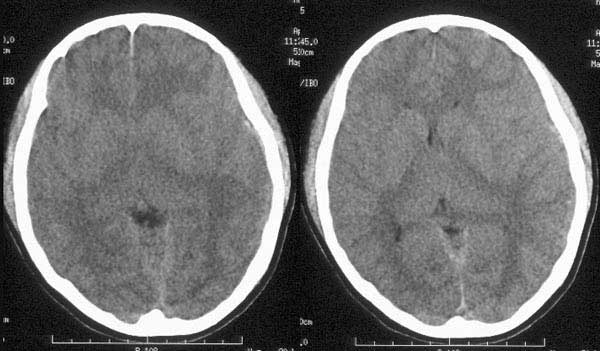

女性,18岁。车祸致伤头部3小时。

ct平扫:左颞骨内板下见细线形高密度出血影,左侧侧脑室受压变窄,中线结构向右侧移位。大脑镰、小脑幕及左枕部脑沟密度增高。鞍上池、环池均显示不清。

ct诊断:1、左颞硬膜下血肿。

2、蛛网膜下腔出血。

3、脑肿胀。